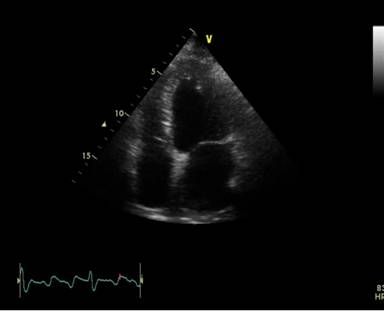

Ecocardiografie : evidentiaza ventricul stang cu dimensiuni la limita superioara a normalului cu disfunctie sistolica severa de ventricul stang (FEVS 30%), prezentand hipokinezie difuza pe peretii VS, dilatare usoara de Ao asc ( 44mm), hipertensiune pulmonara moderata- PAP sistolica 55 mmHg.(Fig. 3, 4,5).

Fig. 5 Hipokinezie sept inferior si perete lateral. 9 fisier HERA 9 movie.